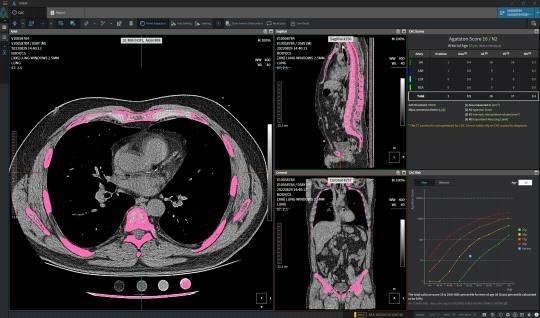

| ▲ 주식회사 뷰노의 흉부 CT 영상으로 폐결절 탐지에서 악성도 평가까지 가능한 기술로 미국 임상 검증 사례 |

| ⓒ 한국보건산업진흥원 제공 |

국제협력연구에서 ▲흉부 CT영상 활용 폐암 조기 진단 인공지능 소프트웨어 ▲소화기관 조기 암질환 대상 복부 최소침습 수술로봇 ▲혈중 내 바이오마커 활용 대장암 선별 체외진단 의료기기 ▲갑상선 기능이상 및 안병증 소프트웨어 의료기기 등 4건의 기술과 해외임상지원에서 ▲ 흉부 CT영상 활용 심폐질환 진단 인공지능 소프트웨어 1건이 그것이다.